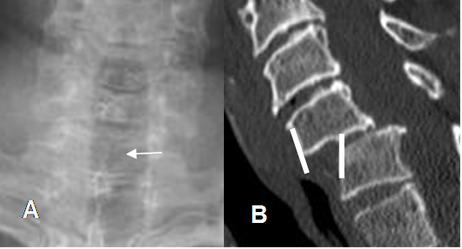

Fig 165. Alteración de apófisis espinosas.

A: Rx AP y B: TAC reconstrucción sagital. No visualización de la apófisis espinosa de C6, por anterolistesis traumática G II.